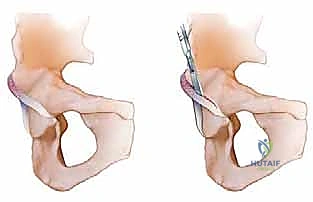

شكل 1أ • تصوير تخطيطي لانحشار الكام. في انحشار الكام، يتم دفع منطقة اتصال رأس وعنق الفخذ الأمامية الجانبية غير الكروية إلى الحُق، مما يخلق إصابة قص وإجهاد للغضروف الحقي على طول الحافة الأمامية العلوية.

شكل 1ب • تصوير تخطيطي لانحشار البنسر. في انحشار البنسر، يتم سحق الشفا الحقي بسبب التغطية الزائدة.